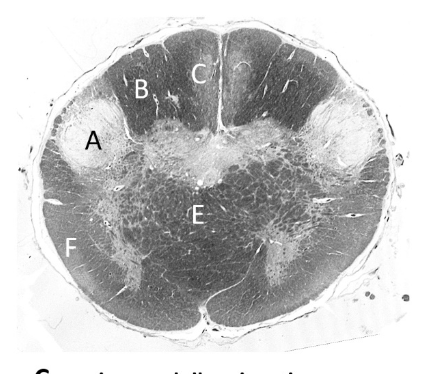

at what level is this?

mid midbrain

what is a?

basis pedunculi/ cerebral peduncle

what is b?

substantia nigra

what is c?

cerebral aqueduct

what is d?

periaqueductal gray

what is e?

superior colliculus

what is f?

medial lemniscus (mb)

what is g?

spinothalamic tract

what is h?

oculomotor nucleus

what is j?

edinger-westphal nucleus

what is k?

oculo-motor nerve fibres